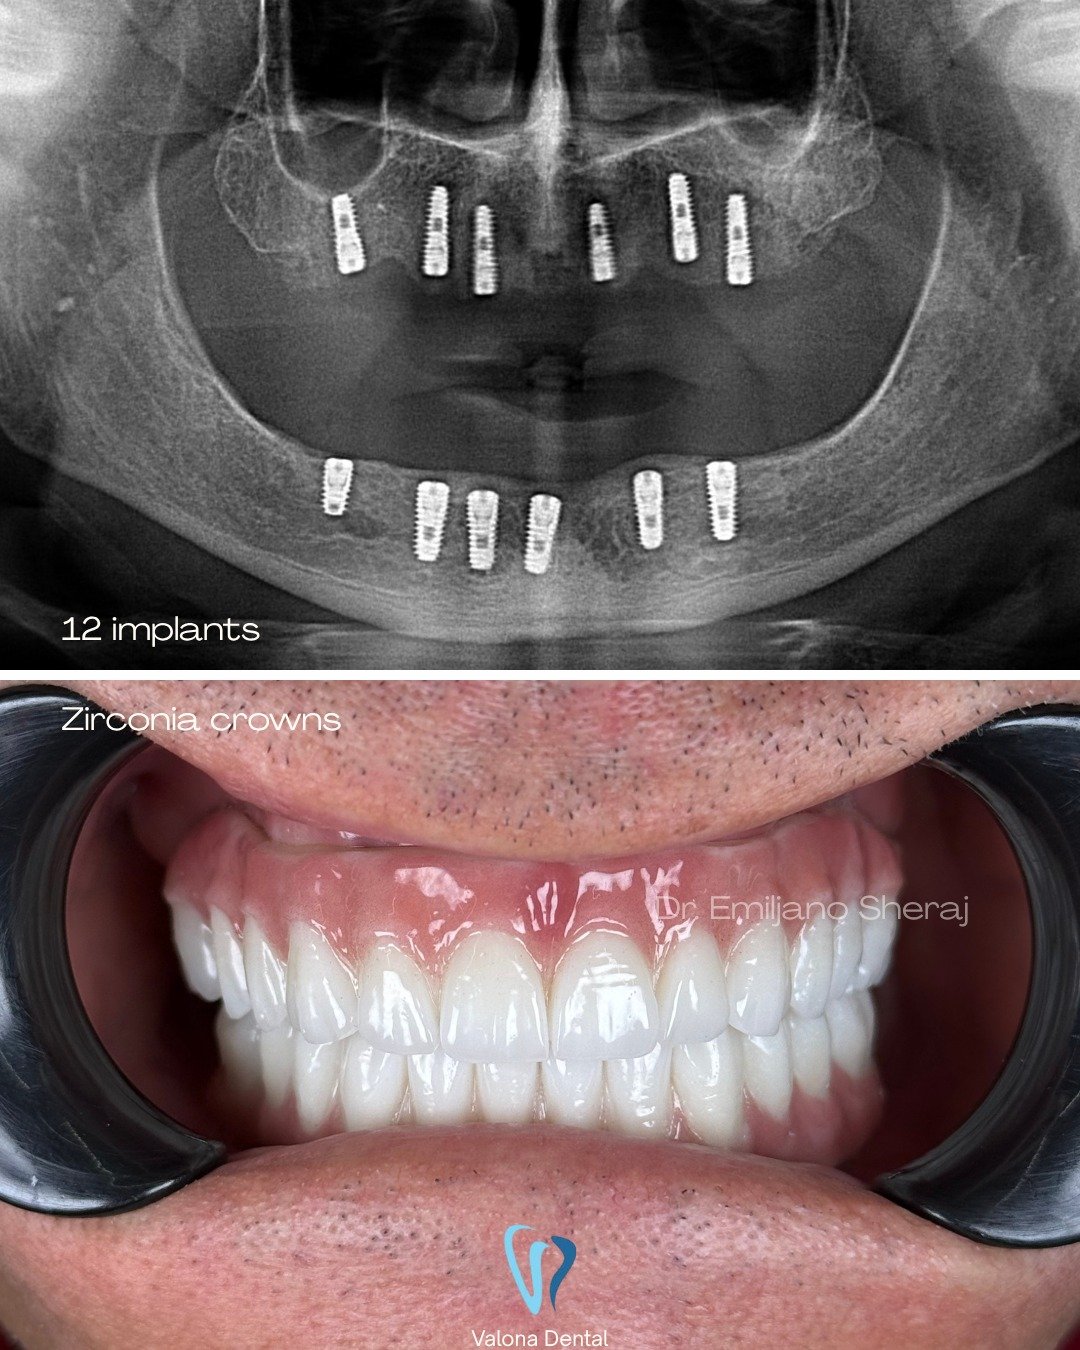

Screenshot